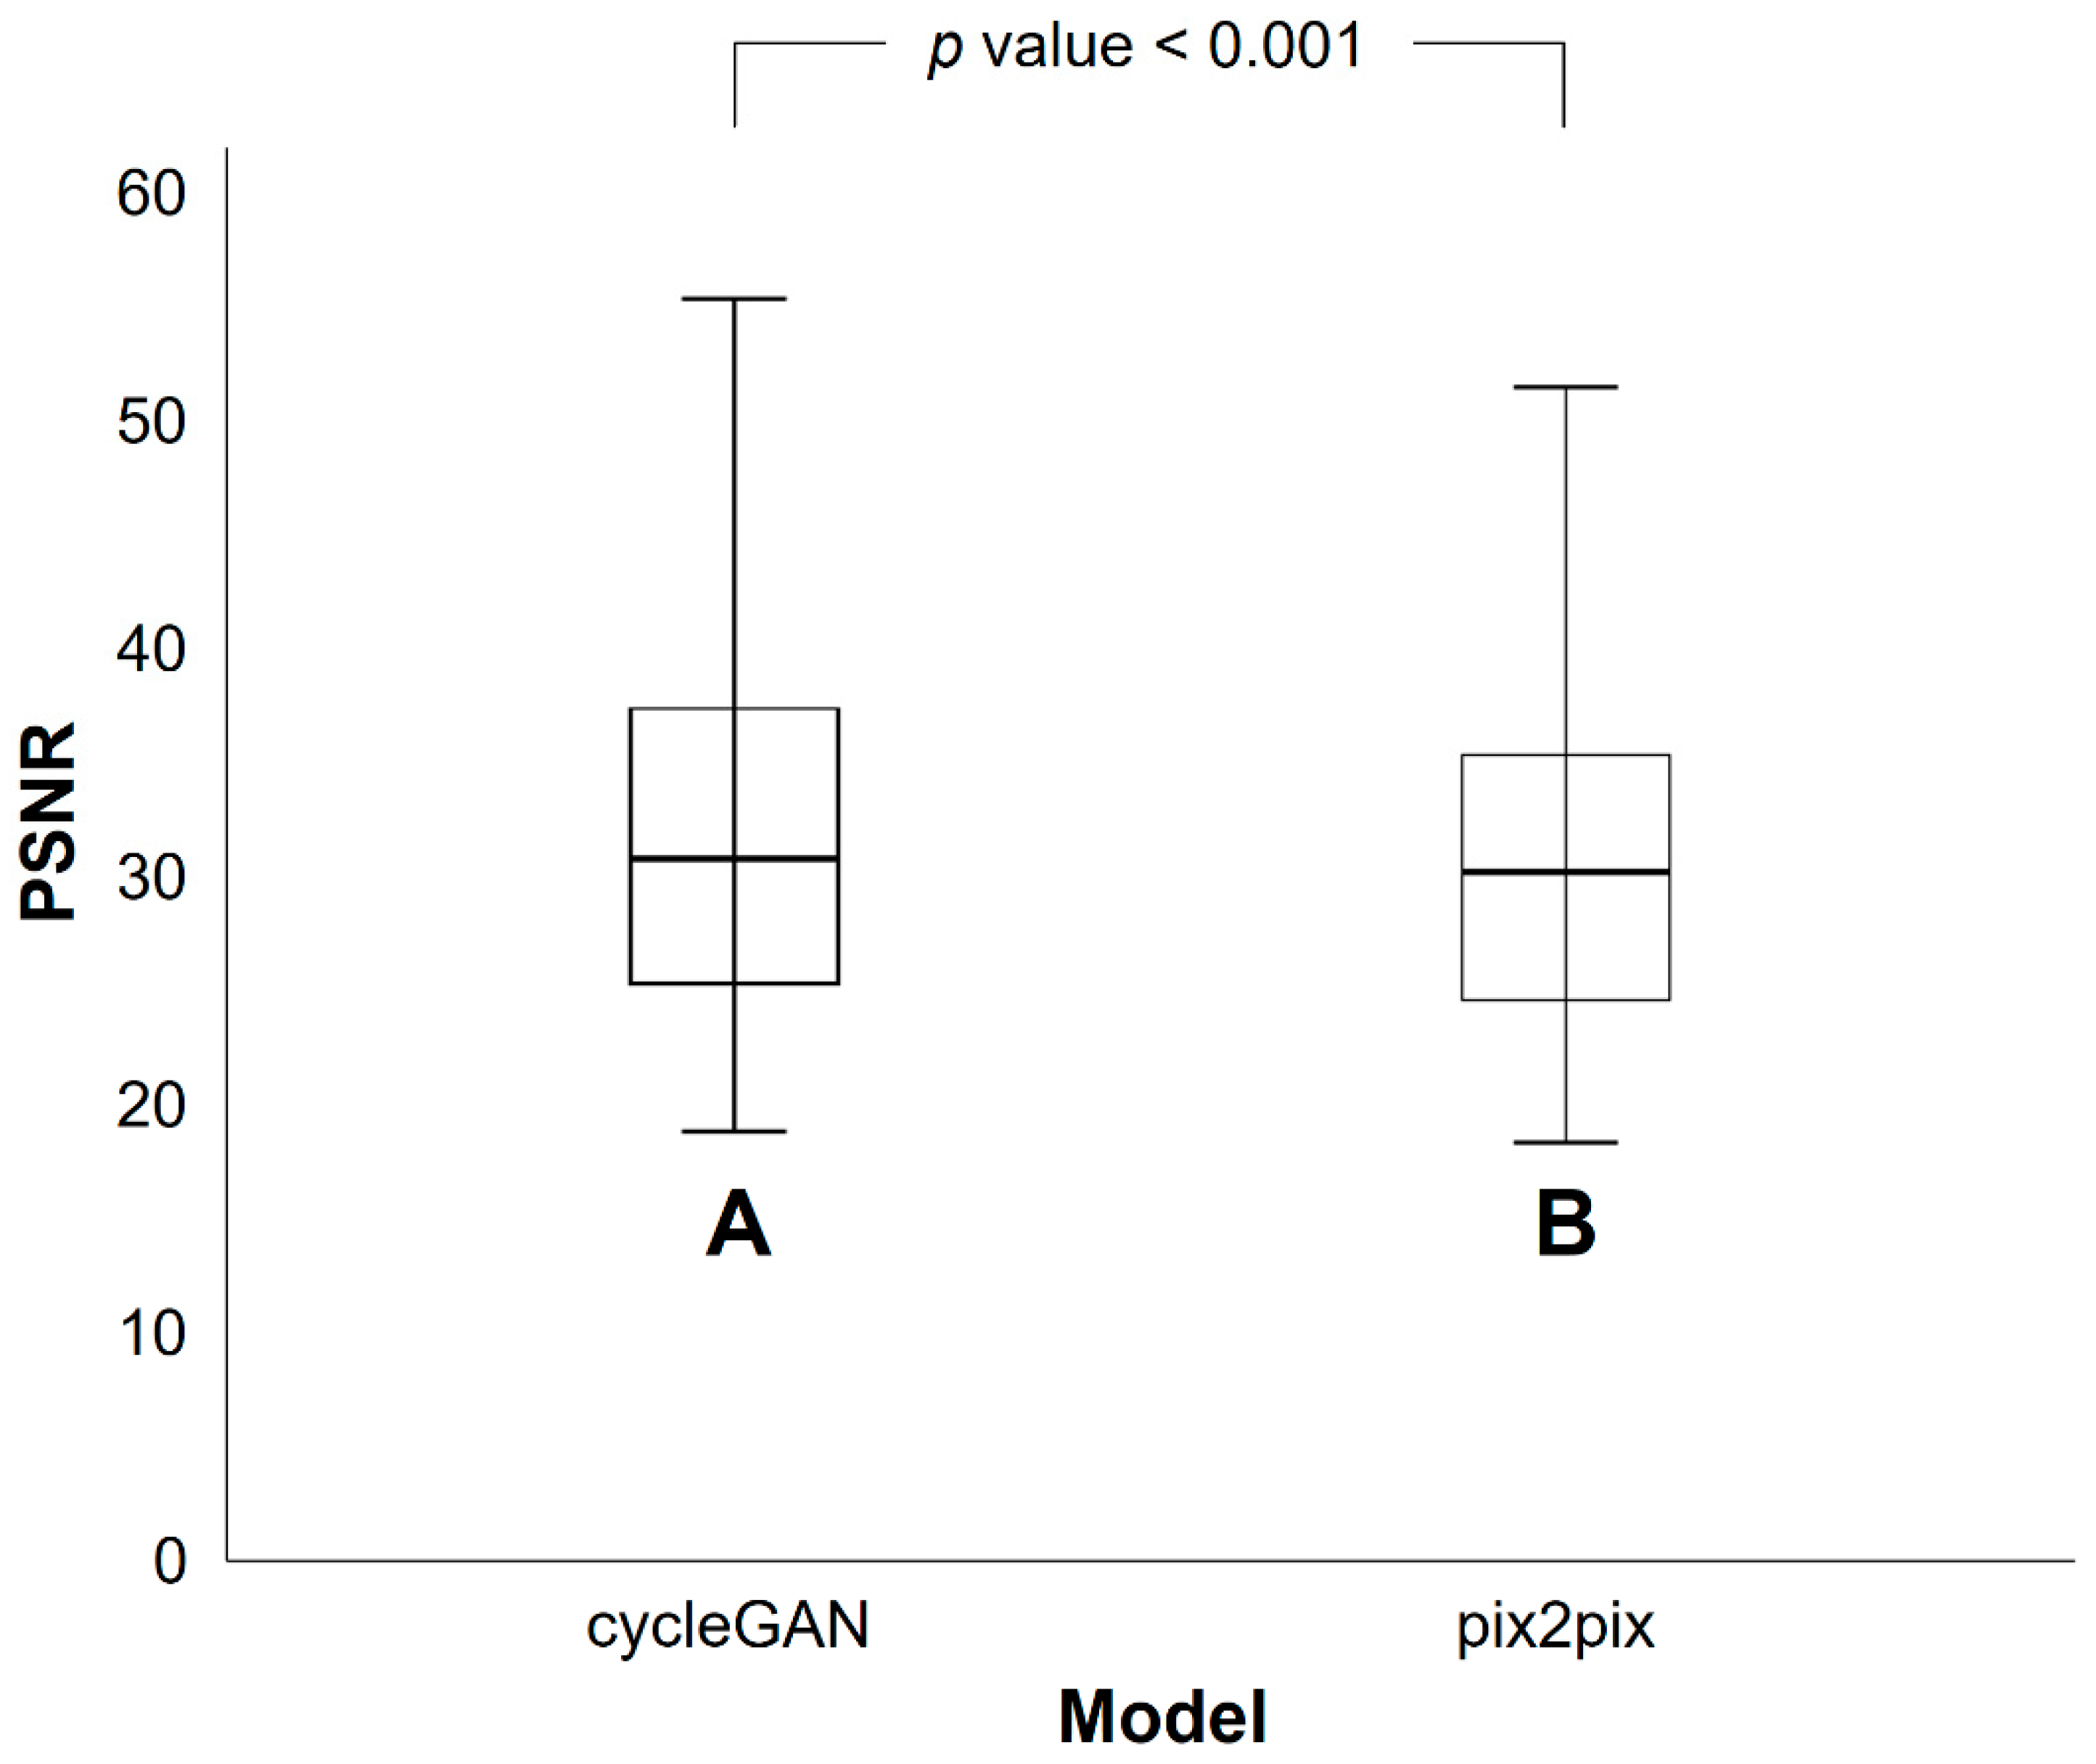

3.2. Differences in SSIM and PSNR Values between PETRE-FDG and PETGE-FDG Images

| CycleGAN Model | Pix2pix Model | p Value * | |

|---|---|---|---|

| Mean | 0.768 | 0.745 | <0.001 |

| Standard deviation | 0.135 | 0.143 |

| CycleGAN Model | Pix2pix Model | p Value * | |

|---|---|---|---|

| Mean | 32.4 | 30.7 | <0.001 |

| Standard deviation | 9.5 | 8.0 |